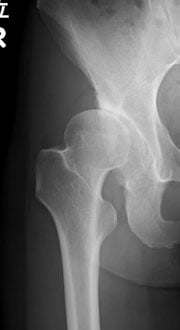

人工股関節全置換術

寛骨臼回転骨切り術

大腿骨頭回転骨切り術

人工股関節再置換術